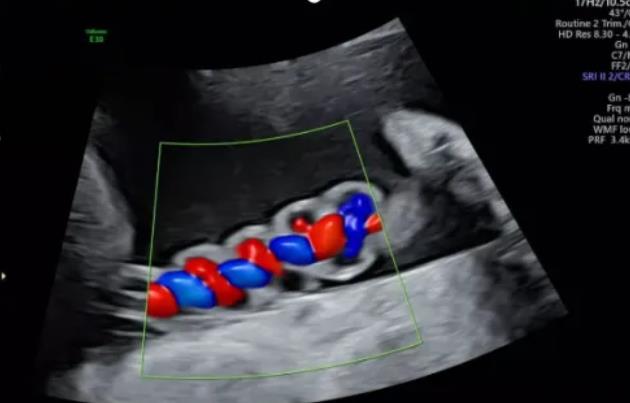

漯河市中醫(yī)院健康科普:超聲檢查之臍帶螺旋

2、臍帶螺旋過松

聲像圖特征:胎兒臍帶縱切面示血管呈平行排列,螺旋稀少,彩色多普勒血流成像示臍帶血管內(nèi)充滿的紅藍(lán)血流呈平行排列,麻花狀螺旋消失。